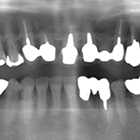

- 歯周病および根尖病巣により骨吸収、動揺が激しく、抜歯適応の歯牙に対し非外科的に歯周治療をNd:YAGレーザーを用いて行い、歯牙の保存を試みた症例

- 症例1:痛くて噛めない、歯がグラグラする 歯茎から血が出る、口臭が気になる